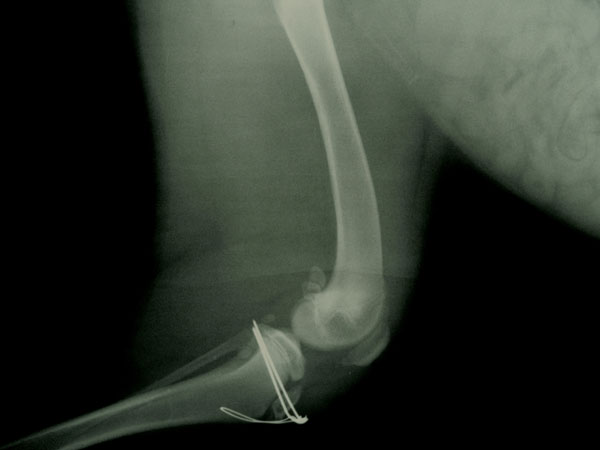

Φωτογραφίες πρίν και μετά το χειρουργείο.

Το χειρουργείο πραγματοποιήθηκε στις 21/10/09

Η αποκατάσταση του κατάγματος έγινε με τοποθέτηση 2 ήλων Kirschner και μεταλλικό ράμμα se tension band wire στην πρόσθια επιφάνεια

της κνήμης.